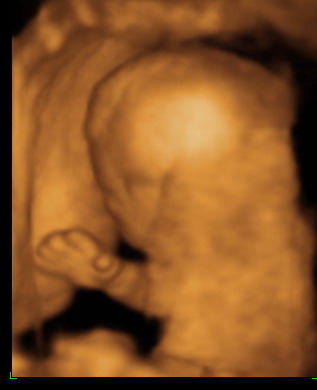

No. Meglepi volt Nektek az UH felvétel, szándékosan nem akartam írni, hogy megyünk.Hétfőn jelentkeztem be, és tegnapra kaptunk időpontot. Annyira édes volt a kis drágánk!! Csak ficánkolt, és ficánkolt, és keresztbe tette a lábacskáit, majd hátat fordított. Nem akartam megmutatni magát, és még a lepénybe is belefúrta a pici testét. A mérések alapján 267 grammosak és kb. 20 cm-esek vagyunk!! :lol: Minden rendben, az orrocskája, a nyaki rendője, a végtagjai, láttuk a szívében a pitvarokat és kamrákat, a vesécskéjét, a húgyhólyagját, a pici agyacskáját, mindent!!! :lol: Hihetetlen élmény volt!!!!

Kati, mi 4d-n Budán voltunk a 4d Genesis kft-nél. Azt ajánlották itt a babaneten egy másik fórumon.

Találtam Gödöllőn is egy privát ultrahangot, 4D-set, fel is hívtam, és annak ellenére, hogy sokkal közelebb lett volna, nem azt választottam. NAgyon nem volt szimpatikus a telefonban. A 4D Genesis pedig már a telefonban is sok infót elmondott, mit fog csinálni, mit néz, mit mér, mit kapok a pénzemért, stb. Úgyhogy itt voltunk Apácskával.